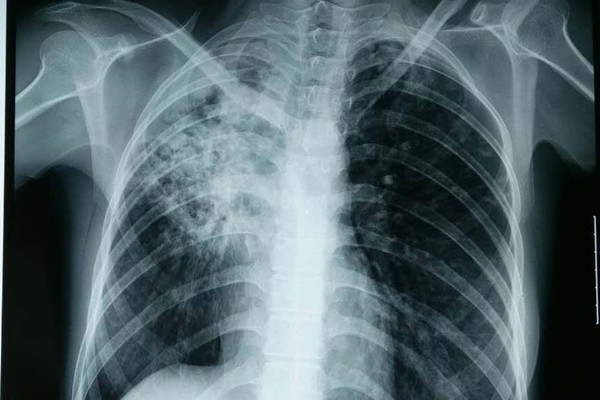

结核性胸膜炎是结核杆菌及其自溶产物、代谢产物进入超敏感机体的胸膜腔而引起的胸膜炎症。属肺外结核病的一种,2000年被卫生部批准的我国新的分类法则将其分类为结核病的第四类型。

据悉我国结核性胸膜炎大多数由人型结核菌所引起。分析其感染途径主要有五种

分析得出结核杆菌直接遍及胸膜是结核性胸膜炎的主要发病机制。那么结核性胸膜炎怎么治疗呢?目前临床常见的有抗结核药物治疗、中西医结合治疗、胸腔抽液治疗等。